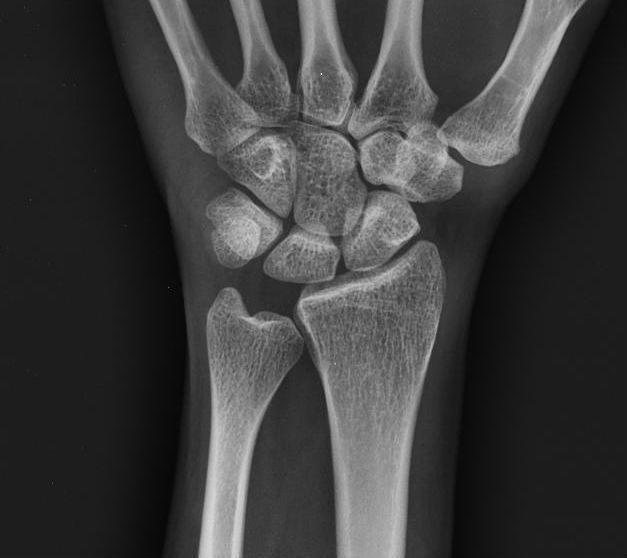

Diagnosis? Classification

Keinboch’s - Litchman Classification

Imaging to help define collapse of lunate